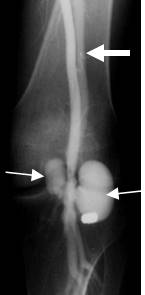

Fig 142 I. Lesión compleja.

Arteriografía. Herida por proyectil de arma de fuego. Hay formación de seudoaneurismas en la arteria poplítea (Flechas delgadas) y visualización precoz de las venas poplítea y femoral superficial distal, por fístula AV asociada. (Flecha gruesa).